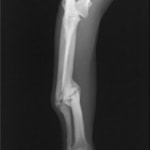

症例3:キルシュナーワイヤーのピンニングによる整復

ペルシャ猫 11ヶ月齢 雄

他院にて左大腿骨遠位の成長板骨折(salter-harrisⅠ型)が認められており、治療相談を目的として来院。当院にて、キルシュナーワイヤーを用いたピンニングにより骨折部位の整復を行いました。術後の経過は良好で、現在も経過観察中です。

術前レントゲン

術後レントゲン